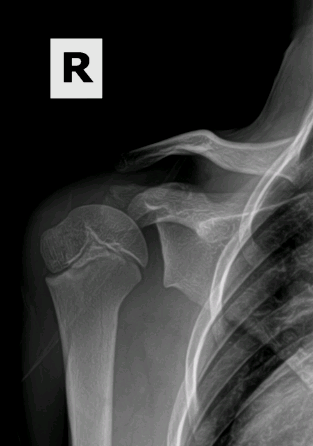

This 13 year old patient presented with a 2 month history of shoulder pain. On exam, the patient had a markedly diminished range of motion of the shoulder. The patient had been playing year round baseball since age 10 and pitches year round. X rays of his Left throwing shoulder (photo1,2,3) reveal a markedly widened growth plate from the repetitive stress of pitching and a low amount of time to heal. His right shoulder (photo 4) demonstrates what a normal proximal humeral growth plate should look like. After 3 months of rest and physical therapy to restore the normal motion of the shoulder, his growth plate has returned to a more normal appearance (photo 5) and he has gone on to safely return to pitching.